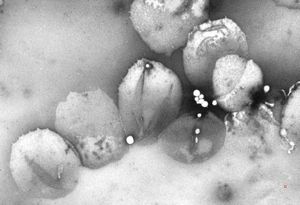

chylomicrons … negative staining